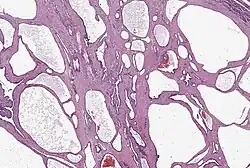

Pankreastumorzellen können Ähnlichkeit mit Zellen der Gänge (duktal), der Azini und Langerhans-Inseln aufweisen, aber auch gemischten Charakter haben.[22] In der Regel richten sich die Pathologen nach der WHO-Klassifikation bösartiger Tumoren, derzeit in der Ausgabe von 2019.[23] Die meisten bösartigen Tumoren (Malignome) werden danach als Varianten des duktalen Adenokarzinoms bezeichnet, eingestuft von hochdifferenziert bis undifferenziert.

Bei den Adenokarzinomen kann man im Mikroskop je nach ihrem Entartungsgrad noch schleimgefüllte Drüsenschläuche mit Zylinderepithel erkennen („duktaler Typ“). Die Nervenscheiden sind fast immer tumorinfiltriert. Charakteristisch ist außerdem eine Verdichtung des umgebenden Bindegewebes („desmoplastische Reaktion“), die in den bildgebenden Verfahren schlecht vom eigentlichen Tumor zu unterscheiden ist. „In der aktuellen WHO-Klassifikation werden die seltenen, prognostisch relevanten Subtypen wie das hochmaligne adenosquamöse Karzinom oder das niedrigmaligne Kolloidkarzinom [(muzinöse nichtzystische Karzinom, mikroskopisch „Schleimseen“)] deutlich untereinander und vom duktalen Adenokarzinom […] abgegrenzt“.[25]